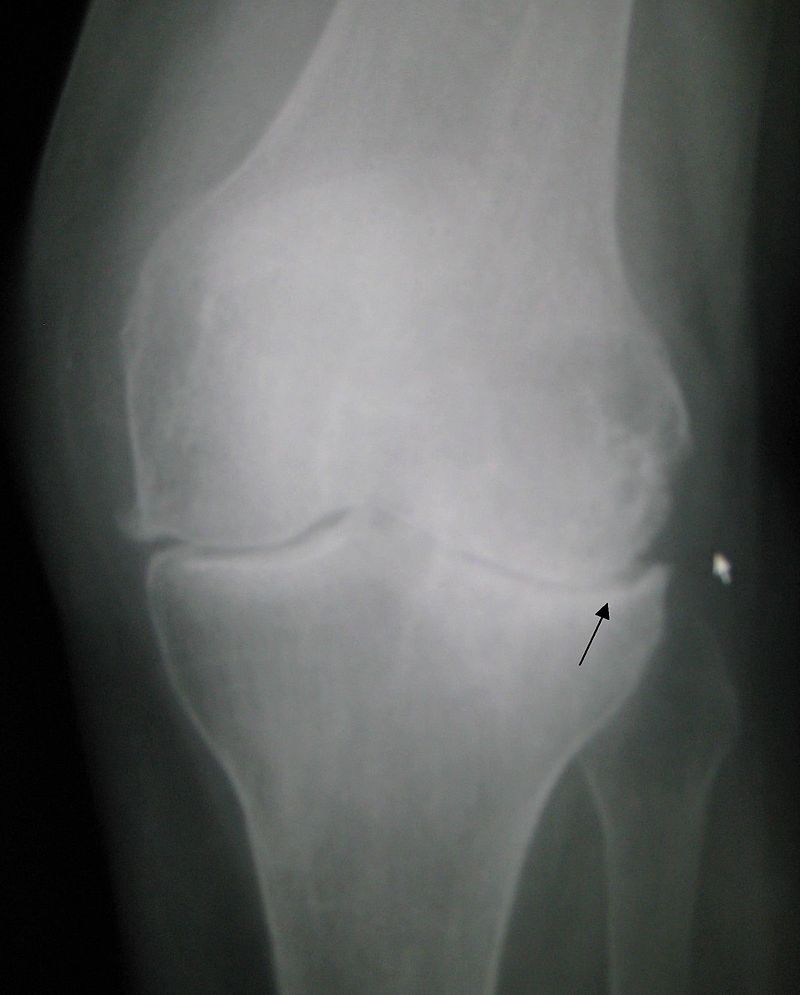

Xray of Osteoarthritis

This xray shows the classic joint space narrowing of Osteoarthritis as well as osteophytes and some changes in bone density

This xray shows the classic joint space narrowing of Osteoarthritis as well as osteophytes and some changes in bone density